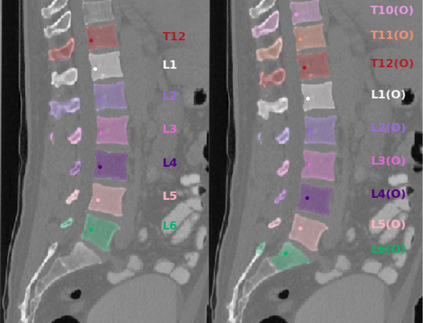

Vertebrae localization, segmentation and identification in CT images is key to numerous clinical applications. While deep learning strategies have brought to this field significant improvements over recent years, transitional and pathological vertebrae are still plaguing most existing approaches as a consequence of their poor representation in training datasets. Alternatively, proposed non-learning based methods take benefit of prior knowledge to handle such particular cases. In this work we propose to combine both strategies. To this purpose we introduce an iterative cycle in which individual vertebrae are recursively localized, segmented and identified using deep-networks, while anatomic consistency is enforced using statistical priors. In this strategy, the transitional vertebrae identification is handled by encoding their configurations in a graphical model that aggregates local deep-network predictions into an anatomically consistent final result. Our approach achieves state-of-the-art results on the VerSe20 challenge benchmark, and outperforms all methods on transitional vertebrae as well as the generalization to the VerSe19 challenge benchmark. Furthermore, our method can detect and report inconsistent spine regions that do not satisfy the anatomic consistency priors. Our code and model are openly available for research purposes.